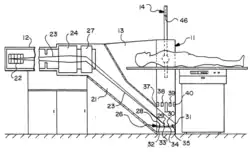

Electron Beam CT (EBCT), another major innovation in CT imaging sought to eliminate mechanically moving parts entirely by employing both a static detector array and a static X-ray source. This was achieved using a large semi-circular tungsten anode made of multiple arcs, across which an electron beam was electronically swept. One such system, the Imatron C-100, was developed by Douglas P. Boyd at the University of California, San Francisco, and introduced in 1981, offering an unprecedented temporal resolution of 33–100 ms.[19]

The scanner featured an electron gun and magnetic beam deflection system, similar to those in cathode-ray tubes (CRTs), allowing the electron beam to be rapidly steered across multiple 6-foot circular tungsten anode arcs—four in the initial system—covering 210°. The entire electron path was contained within a vacuum chamber, resulting in a large physical footprint, particularly on one side of the gantry. The upper part of the system was equipped with two rows of detectors, comprising 432 scintillator-photodiode elements also spanning 210°, designed to capture the X-ray fan beam generated by the rapidly moving focal spot. With four anode tracks and two detector rows, the system could generate eight image slices in under 1s.[13]

This design was specifically optimized for cardiac imaging, as the heart's rapid motion makes it highly susceptible to motion artifacts. It enabled advanced applications such as coronary calcium scoring and other heart-related diagnostics.[13] EBCT was also used for pediatric imaging, where patients often struggle with breath-holding or remaining still during scans. Only much later did modern CT systems, with multi-detector and dual-source technology, achieve comparable temporal resolution, eventually displacing EBCT from the market. Its decline was due to several limitations: a large footprint, limited versatility for general imaging, high acquisition and maintenance costs, and lower spatial resolution compared to newer technologies.